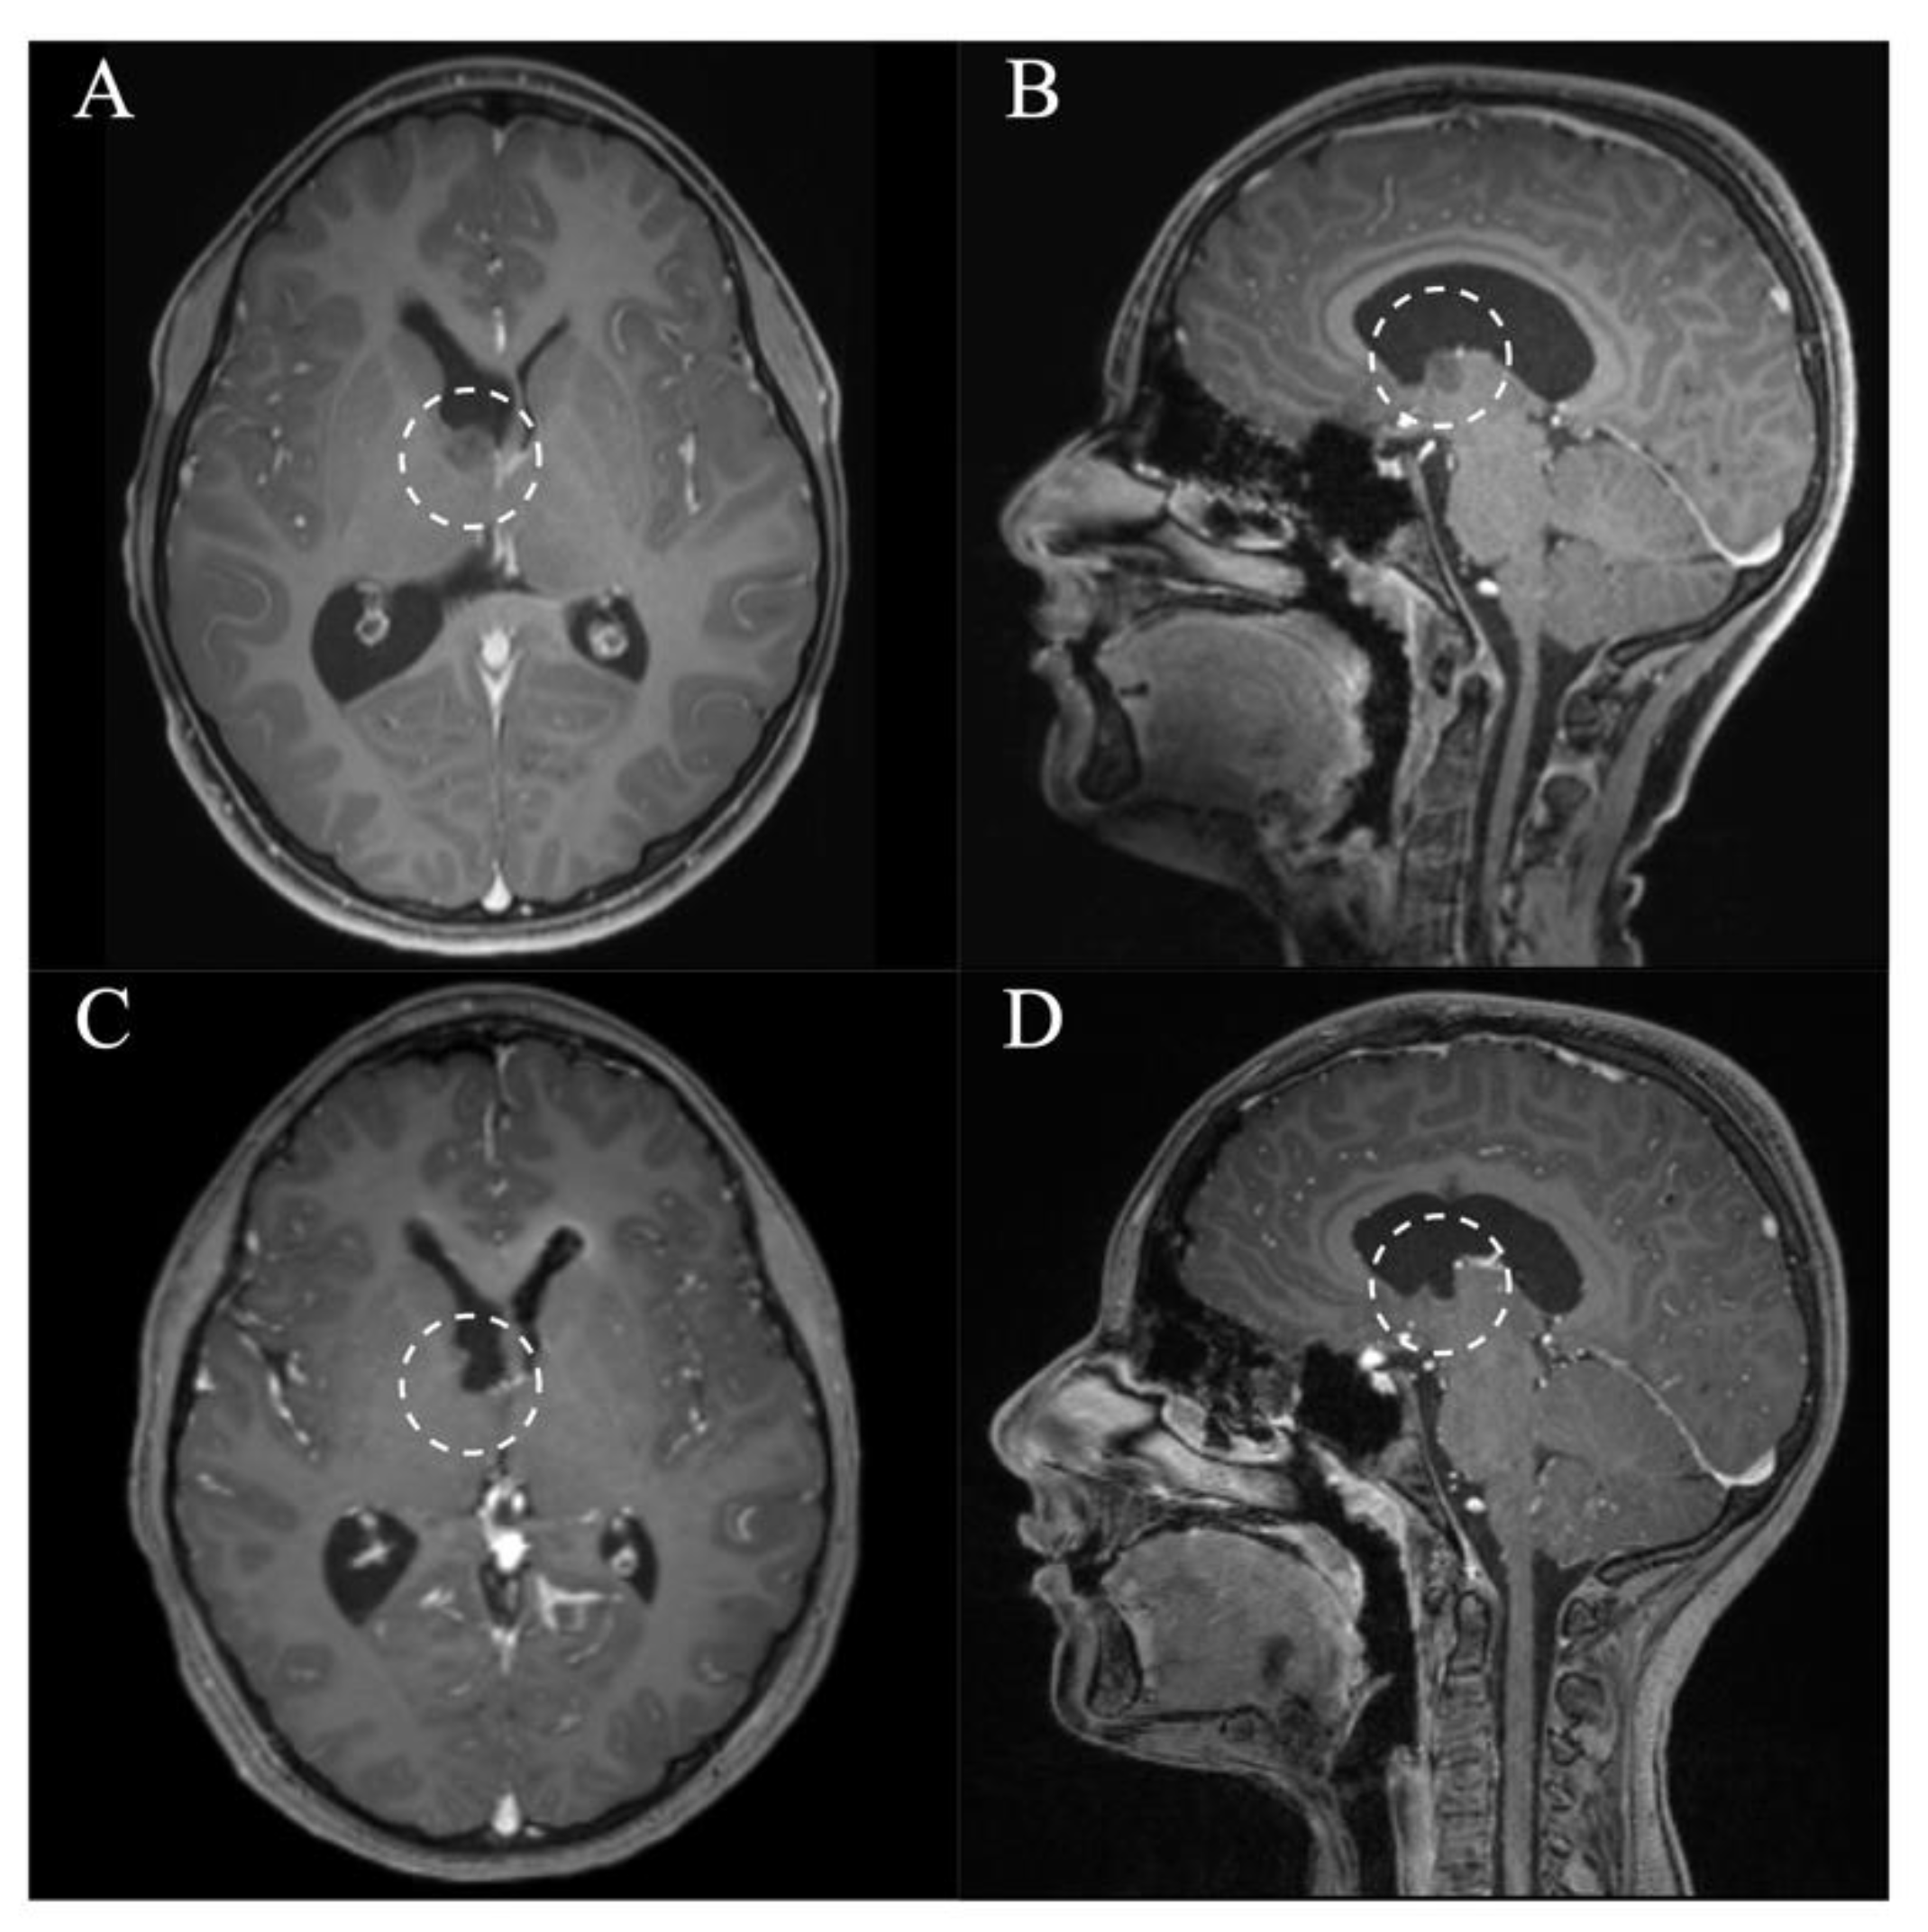

In all patients, a GTR/NTR could be achieved (Table 3). The pre- and postoperative scans of cases no. 3, 6, and 7, which were all treated through an EA approach and case no. 8, which was treated through a PE approach, are shown in Figure 3, Figure 4, Figure 5 and Figure 6. In one patient (case no. 5), due to her advanced age, we referred from resecting the vascularized capsule of the colloid cyst, achieving NTR. The mean surgery time was 163.6 ± 54.2 min (range 82–240 min) and the average blood loss was 142.5 ± 90.4 mL (range 50–300 mL). The PE approach was associated with lower mean blood loss than the EA approach (87.5 ± 47.8 mL vs. 197.5 ± 93.2 mL, p = 0.114). In four patients (50%), a total of six postoperative complications occurred, of which all were transient. Two patients (25%) showed transient cognitive impairments after resection of a colloid cyst, most likely directly associated with the endoscopic approach. The remaining four transient complications were unrelated to the use of endoscopy or NUA (Table 3). The two patients with neuropsychological evaluation showed postoperatively scores of 18/30 and 25/30 points, respectively, with a documented improvement in both patients at follow-up (18/30 to 24/30 points within 35 days and 25/30 to 30/30 points within 114 days). With regards to the remaining adult patients, no evaluation was carried out, because there was no evidence of neurocognitive deficits subjectively. In the two children with intraventricular lesions, no postoperative neurocognitive assessment was performed (due to autism disorder in the context of tuberous sclerosis in one case and due to the very young age of 5 months in the other case) (Table 3). At follow-up (15.9 ± 6.3 months; range 6.8 to 23.2 months), all patients showed improved or unchanged mRS when compared to the mRS at discharge. Complete regression or improvement of the preoperative complaints was seen in all patients, while MRI at follow-up showed no recurrence in any of the cases (Table 3).

Figure 3. Case 3. Axial and sagittal MR images, T1-weighted sequences with contrast medium preoperatively (A,B) and immediately postoperatively (C,D) after resection of the intraventricular meningeoma via a right parietal endoscopic-assisted approach.